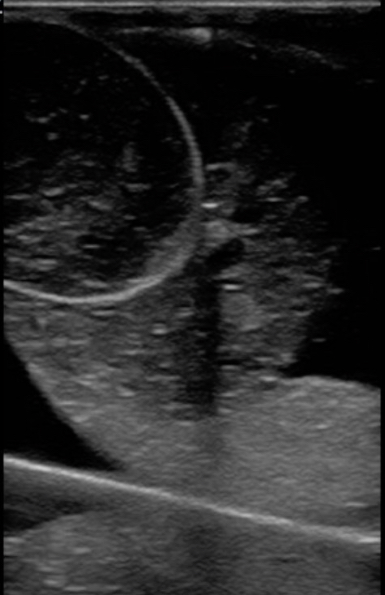

Figure 14. A model created with half the recommended gelatin concentration used as an example of testicular Infarction with hydrocele. The model was allowed to settle in place in the refrigerator and the psyllium collected to one side.

Figure 15. A model with a cherry and half the recommended concentration of gelatin used to demonstrate a penetrating foreign body with testicular rupture and hematocele.